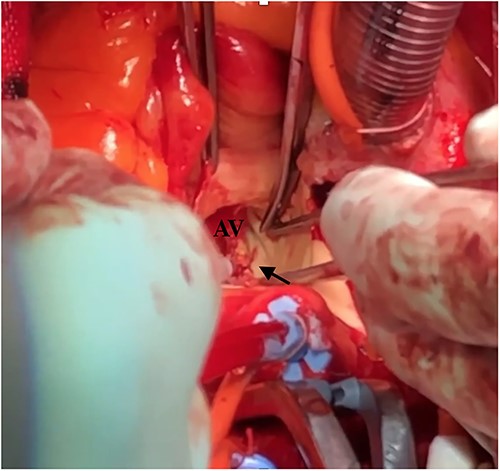

Intraoperative finding shows a tear at the left non-commissure. AV: aortic valve.

Under light sedation and local anesthesia, a 26-mm SAPIEN 3 valve was deployed with 1.5 ml less balloon inflation to avoid excessive pressure on the aortic annulus. After valve deployment, TTE revealed a small pericardial effusion. Pericardial drainage was performed, and blood was drained. Intraoperative angiography revealed a small amount of contrast leakage around the ascending aorta (Fig. 2). Transesophageal echocardiography (TEE) under deep sedation revealed a hematoma at the aortic annulus with blood inflow (Fig. 3a and b). Emergent open surgery was performed. The aorta was exposed through a median sternotomy. Cardiopulmonary bypass was established via the ascending aorta and the right atrium, and the aorta was cross-clamped. Antegrade cardioplegia was administered via an aortic root cannula, and cardiac arrest was achieved without complications. The prosthetic valve was firmly adherent to the aortic annulus and carefully removed. A tear in the non-left coronary commissure was sutured using 5–0 Prolene (Fig. 4). An INSPIRIS 21 mm valve (Edwards Lifesciences, Irvine, CA, USA) was implanted. The patient was discharged on postoperative day 14 after rehabilitation. One year after surgery, TTE revealed no paravalvular leakage and a preserved ejection fraction of 34%.